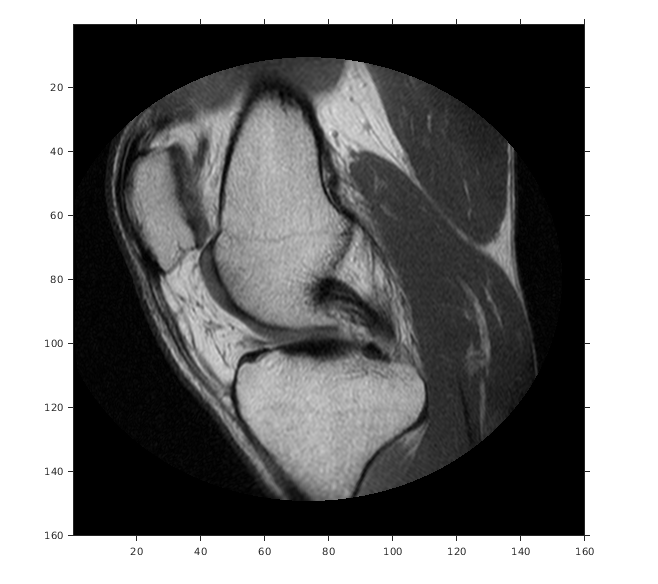

Считайте 2D полутоновое изображение колена в рабочую область.

m = dicominfo('knee1.dcm');

A = dicomread(m);

Создайте объект imref2d, задав размер и разрешение пикселей. Файл DICOM содержит поле метаданных PixelSpacing, который задает разрешение изображения в каждой размерности в миллиметрах на пиксель.

RA = imref2d(size(A),m.PixelSpacing(2),m.PixelSpacing(1))

Отобразите изображение, включая пространственный ссылочный объект. Координаты осей отражают мировые координаты. Заметьте, что координата (0,0) находится в левом верхнем углу.

figure

imshow(A,RA,'DisplayRange',[0 512])